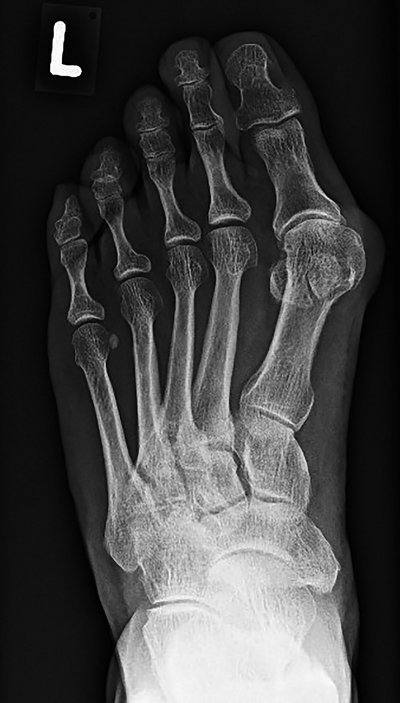

„Jede Gewerkschaft wäre entsetzt. Die Füße leisten an 365 Tagen im Jahr, fast rund um die Uhr, ohne Feiertag, Urlaub oder Wochenende, Schwerstarbeit. Und das häufig unter erschwerten Bedingungen. Die moderne Schuhmode stellt eine zusätzliche Belastung dar“, benennt er mögliche Ursachen der Entstehung des Hallux valgus. So sind etwa neun von zehn Frauen betroffen, die häufig durch falsches Schuhwerk, beispielsweise das dauerhafte Tragen von hohen Absatzschuhen, ihre Füße belasten. Übergewicht, langes Stehen und Spreizfüße sind weitere Faktoren, welche die Entwicklung eines Hallux valgus begünstigen. „Die Großzehe verdreht sich nach innen, das Grundgelenk der Zehe knickt nach außen ab und verdrängt oder überlagert die zweite Zehe. Aufgrund dieser Fehlstellung verlaufen die Muskeln und Sehnen zu den Zehen nicht mehr zentral über das Gelenk, sondern weiter innen und ziehen die Großzehe im Verlauf immer weiter in eine schiefe Position“, beschreibt Dr. med. Jan Sperling die Fußdeformität.

In Folge der Ausbildung des hervortretenden Großzehenballens drücken die Schuhe. Schmerzhafte Entzündungen können die Folge sein. Weiterhin kann es zu einem vorzeitigen Gelenkverschleiß oder einer Arthrose im Großzehengrundgelenk kommen.